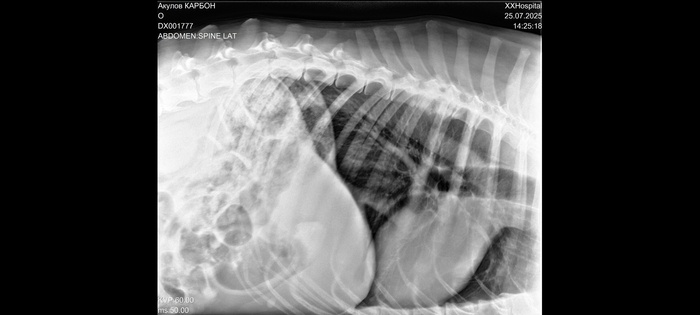

Сделали рентген и анализ крови.

Заключение - проблемы в позвоночнике.